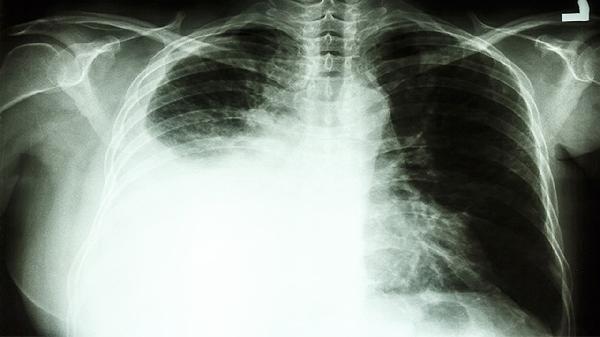

1、总体风险数据

长期吸烟者中,约10%-20%最终会罹患肺癌。这意味着每100个烟民中,可能有10-20人会得肺癌。这个比例看似不高,但相比不吸烟人群0.3%的患病率,风险增加了30-60倍。

2、定期体检筛查

低剂量螺旋CT可以早期发现肺癌,建议50岁以上吸烟者每年检查。